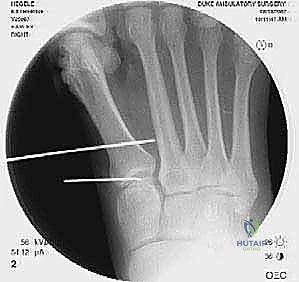

2. التصوير الشعاعي المتقدم

- الأشعة السينية مع تحمل الوزن (Weight-bearing X-rays): صور من الأمام، الجانب، والزوايا المائلة لتقييم زوايا العظام تحت تأثير وزن الجسم.

- تصوير السمسمانيات (Sesamoid view): لمعرفة ما إذا كانت العظام السمسمانية قد خُلعت من مكانها.